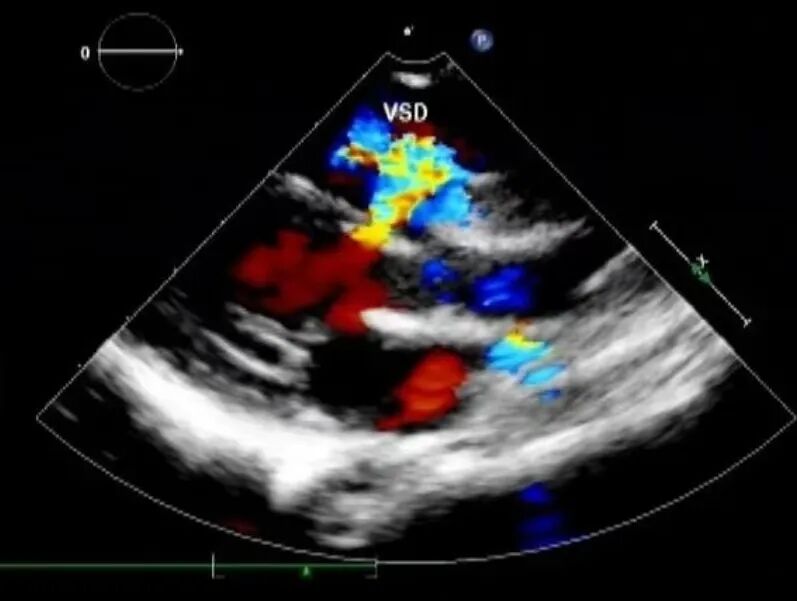

彩色多普勒技术主要用红色和蓝色来显示组织器官内血液的不同流向,颜色的不同能够帮助超声医生分辨血液朝哪个方向流动。如果血液的流动方向朝向探头,图像显示为红色,反之血液的流动方向背向探头,则图像显示为蓝色。因此,图像显示为红色、蓝色与动静脉分类无关。颜色越鲜亮,就说明这里血液流动的速度越快,颜色越暗淡,就说明血液流动的速度越慢。

彩色多普勒常用于观察心脏、血管、脏器供血及肿瘤滋养动脉的多少和走行。在先天性心脏病患者中,根据血流的方向、部位发生的异常情况,彩超可以追踪到心脏壁及间隔上的缺损。应用彩色多普勒技术能找到更多的诊断疾病的信息,为疾病的诊断及治疗提供有效的依据。